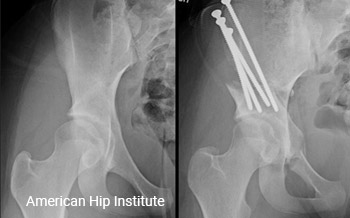

Surgery Observation

Contact us at info@americanhipinstitute.com to schedule observations.